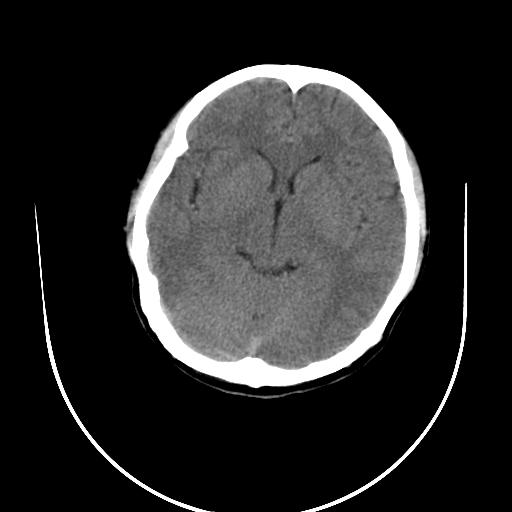

标题: CT10010:女/24岁,癫痫一周,发作时间不固定. [打印本页]

标题: CT10010:女/24岁,癫痫一周,发作时间不固定.

右侧额叶正常吗?

右额叶镰旁饱满.

右侧外侧沟?中央沟?可能有问题,不知以前有没有癫痫过,最好是增强下,排除局部血管畸形等病变

倒数第6幅图中线结构有点偏,而侧脑室额角未见异常,可结合增强扫描。